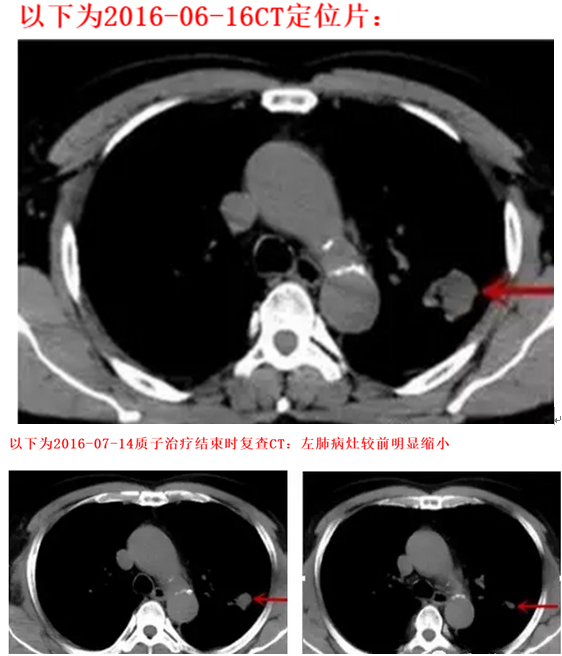

有图有真相,请看质子治疗经过CT图:

质子定位并制定治疗计划,开始行质子放射治疗,左肺上叶病灶,DT68cGE/17f,5f/w。质子治疗几次后,咳嗽、痰中带血的情况明显好转,且质子治疗期间患者无丝毫不适症状,未出现任何副反应。质子治疗结束后复查胸部CT提示病灶较前明显缩小,患者悬着的心终于放下。